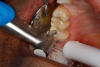

Fig 18. Matrix band in place, injection filled with dual-cure bulk-fill flowable composite.

Figure 18